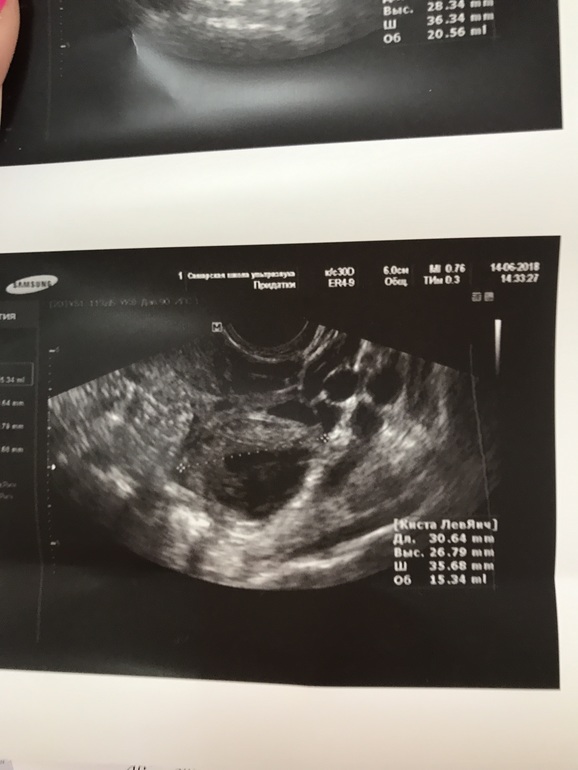

И вот сейчас 22 -й день цикла , была в отъезде , не было возможности делать УЗИ , делала тесты на овуляцию с 9 по 14 дц , но так и не дождалась положительного результата ( брала клеоблю - так и не дождалась улыбку )) не помню точно с какого дня , но неделю точно уже ( т.е с 15 дц ) начались боли в боках и слева и справа , но не прям где яичники , а выше .... эти боли мне прям дискомфорт доставляют ... усиливаются почему-то вечером тли прям когда спать ложусь 🤔 сегодня решила заехать на УЗИ глянуть что там ) и посмотреть была или не была овуляция .... и вот вышла и думаю , что лучше бы не заезжала ... одни неясности .. узитска ни на что не дала гарантий , все у неё под вопросом , и наставила кучу диагнозов 🤦♀️ Вышла вот вся в сметении и расстройствах , может кто разбирается и по фото может понять что и как ?